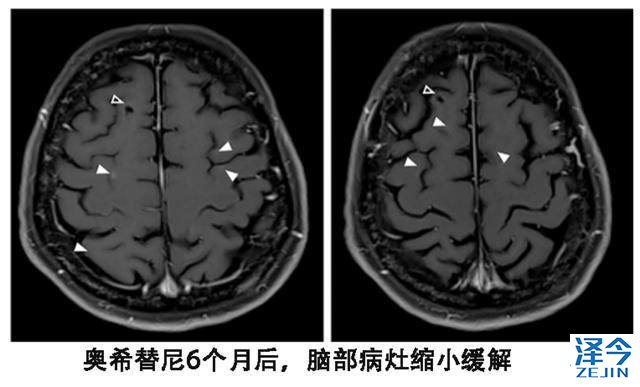

患者尽管血液基因检测T790M阴性,但是依然换用了第三代靶向药物泰瑞沙(AZD9291),每天的剂量为80毫克,结果出现了奇迹。患者的视觉双影没有了,脑脊液的细胞学检查也为阴性,脑部核磁显示脑皮质损伤有所改善。

尽管血液T790M检测为阴性,从换用9291之后,患者脑部病灶稳定了一年,另外脑外的病灶一直处于稳定状态。